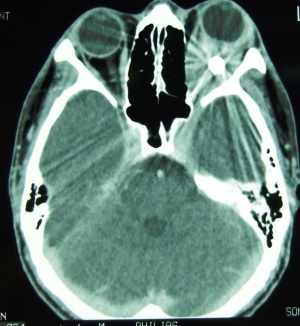

Computerized tomography is the imaging of choice for evaluating suspected orbital and orbitofacial fractures, intraorbital and intraocular foreign bodies and traumatic optic neuropathies. In the trauma setting, it is generally performed as a non-contrast study, with contrast indicated only in cases where there is concern for carotid-cavernous fistula. Axial images are useful in evaluation of the medial and lateral orbital walls, in addition to the medial and lateral rectus muscles. Coronal images are similarly useful in scrutinizing the superior and inferior orbital walls, the superior and inferior rectus muscles, and identifying optic nerve sheath hematoma. [29] While soft tissue window is useful for gross disruptions of the bone and soft tissue changes (EOM, Fat, Optic nerve, Brain, etc), Bone Windows are much more sensitive to detect orbital and orbitofacial fractures and should be viewed in the axial, coronal and sagittal views.

In the setting of orbital wall fracture, CT scan can often be helpful in demonstrating entrapped extraocular muscles. CT typically demonstrates linear floor fractures with minimal displacement and little or no soft tissue displacement in the maxillary antrum. However, associated soft tissue swelling, fat stranding, and muscular hematoma can often make radiographic interpretation difficult, especially in children where CT findings of entrapped extraocular tissues can be minimal. This emphasizes the importance of clinical exam using assessment of extraocular motility and forced ductions. Finally, CT can also be used o estimate the fracture area, which can be utilized as criterion for operative repair. [30]

In situations where a detailed clinical examination is not possible and there is a high suspicion of globe disruption, a CT scan may be indicated.[31] In patients with a clinical diagnosis of traumatic optic neuropathy, CT can be employed to asses for optic nerve canal fracture, foreign body, or bony impingment on the nerve.[32] It can also be employed for intraoperative navigation of the orbitofacial skeleton with 3-D modeling, in which images are acquired in the 0.6 – 1 mm formats. 3D reconstructions may be performed for patient education and treatment planning, which may be used for prebending orbital implants.

CT can also aid in the diagnosis of “open globe” injuries, defined as a full-thickness disruption of the sclera or cornea of the eye. Findings suggestive of an open globe injury on CT include a disruption of the globe contour, change in globe volume, variation in anterior chamber depth, and finally intraocular air, blood or foreign body. In one study, the sensitivity and specificity of detecting open globe injuries with CT was estimated at 75% and 93%, respectively. Therefore, although useful in the evaluation of traumatic injury to the globe, CT should not be relied upon solely for the assessment of open globe injuries. [29] Finally, CT scans of the orbits and face and not infrequently to assess completeness and accuracy of orbital reconstruction following fracture repairs, especially when postoperative complicaitons such as strabismus, motility disorders or optic neuropathy.